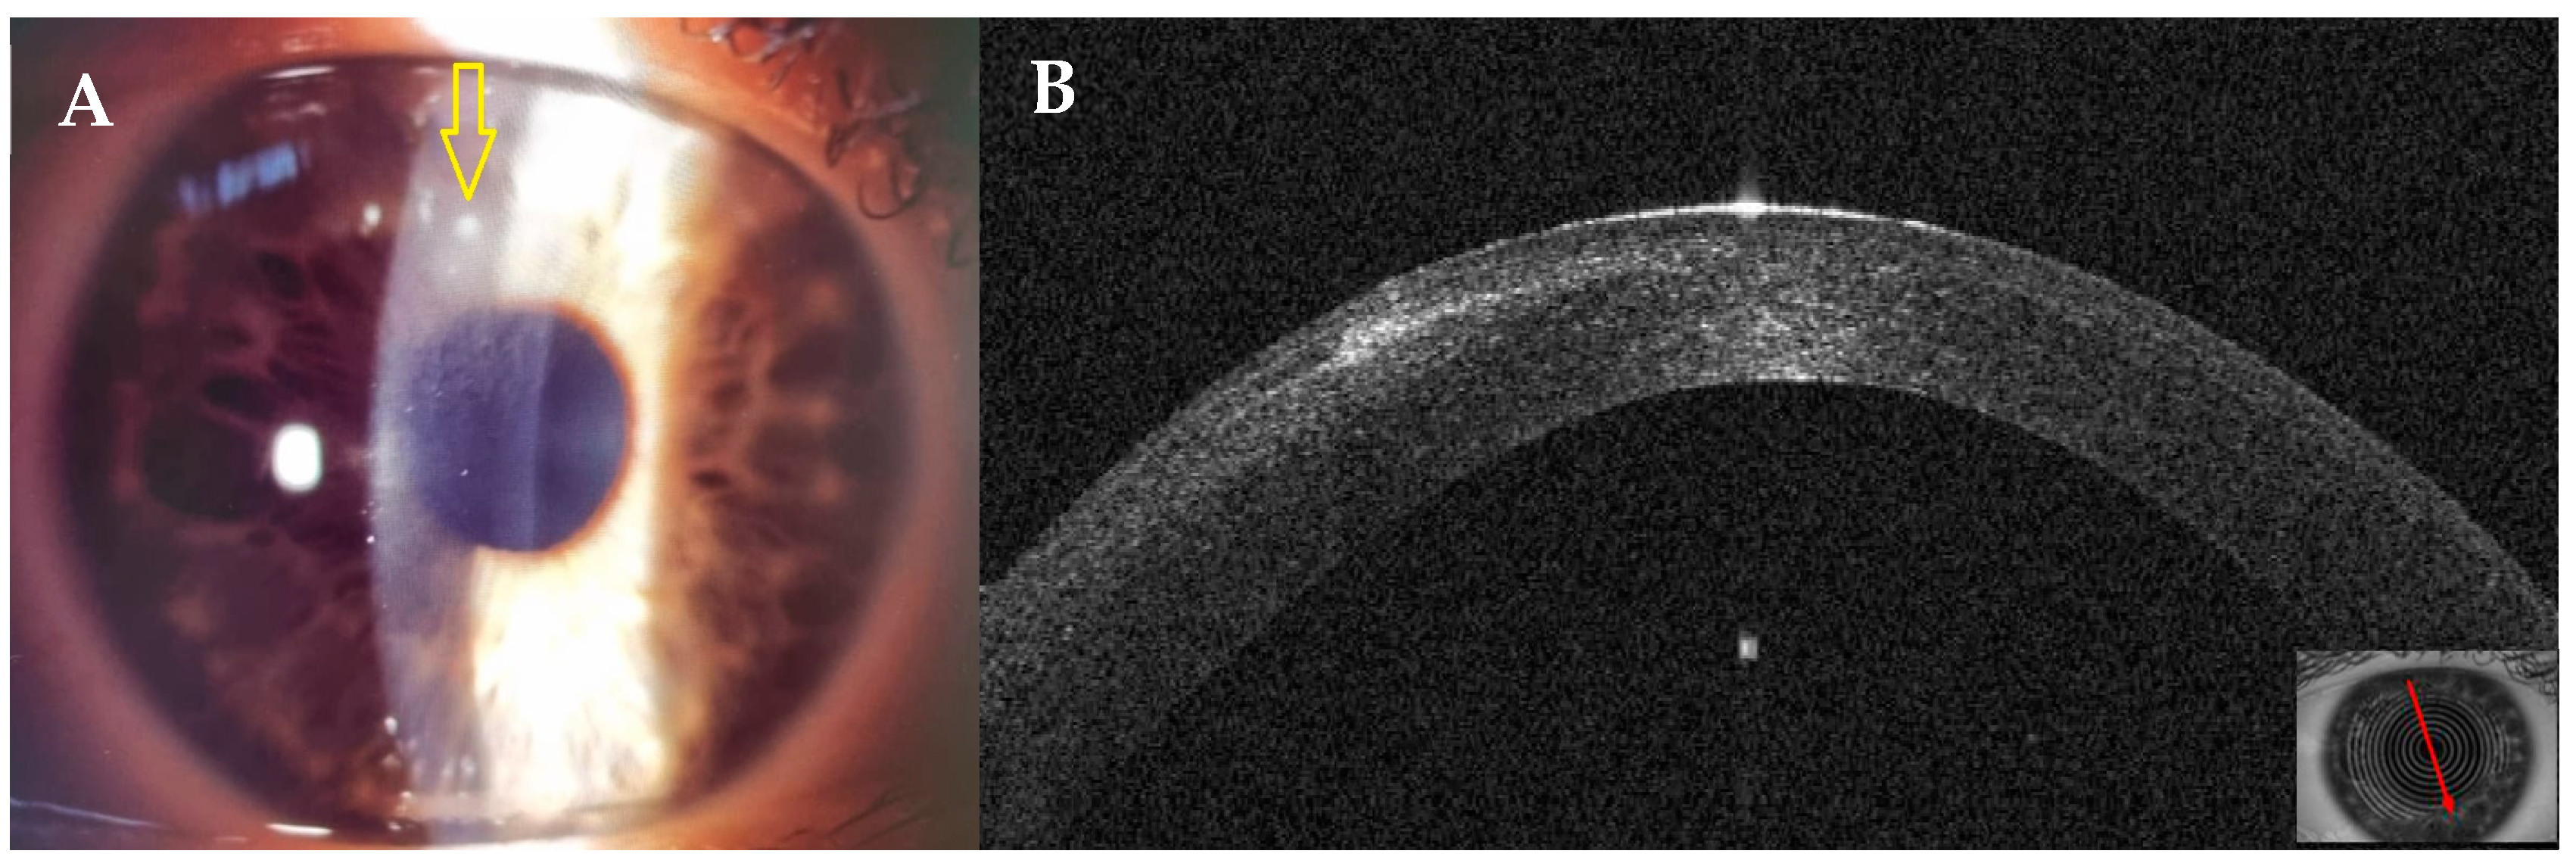

3.1. Patient #1